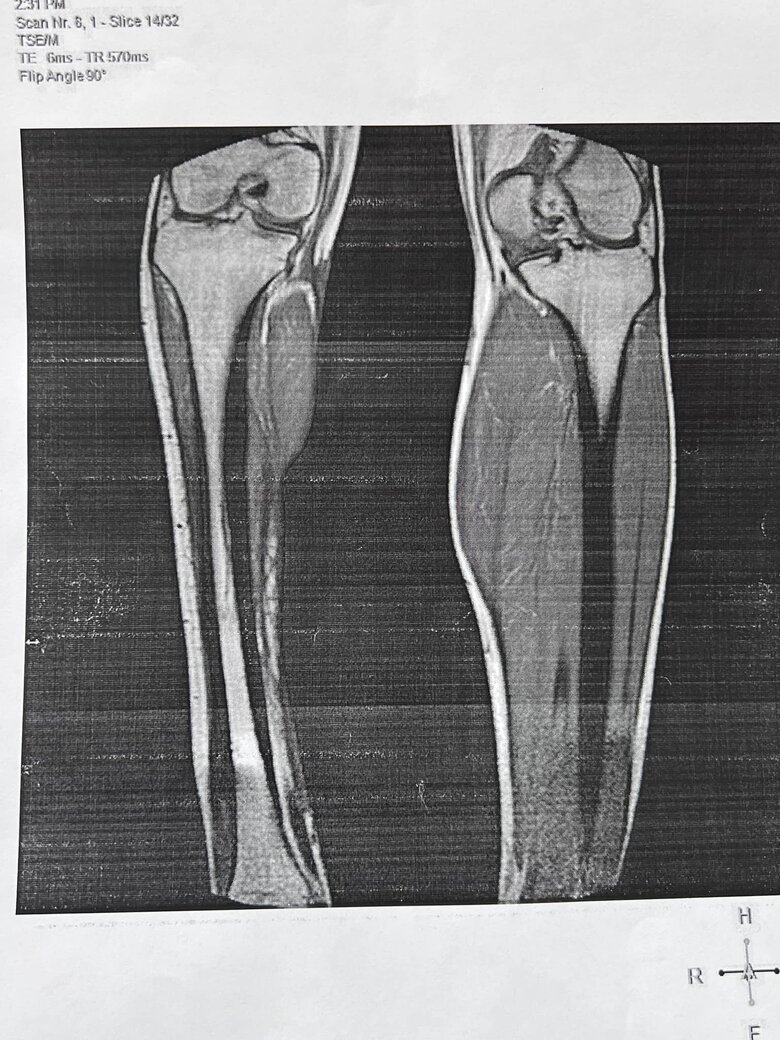

Почти год назад военнослужащему была установлена 3 группа инвалидности. Из-за увольнения из рядов ВСУ в начале августа его документы поступили в Харьковскую МСЭК №3 – повторно.

Ранее украинский воин Дмитрий Олейник в фейсбуке рассказал о случившемся с ним случаем в Харьковском областном центре медико-социальной экспертизы (МСЭК), требуя увольнения Ларисы Буничевой с должности руководителя Харьковской областной МСЭК. По словам ветерана, перенесшего 15 операций, Буничева заявила: "Так зачем ты оставил свою ногу, надо было бы ее отрезать - и была бы 2 группа".